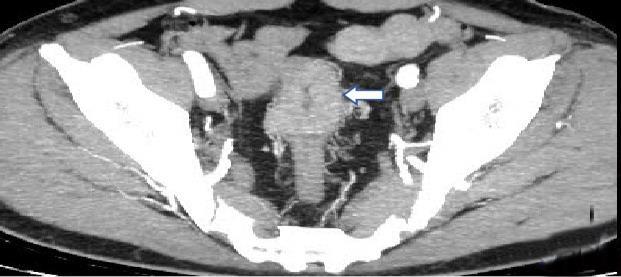

• 计算机体层摄影血管造影在腹腔镜结肠癌根治术前评估中的应用效果

2025, 31(6):24-31. DOI: 10.12235/E20240177

摘要 (181) HTML (147) PDF 4.65 M (171) 评论 (0) 收藏

摘要:目的 分析计算机体层摄影血管造影(CTA)在腹腔镜结肠癌根治术前评估中的应用效果。方法 回顾性分析2021年1月-2024年2月于该院接受腹腔镜结肠癌根治术的120例患者的临床资料。其中,60例行常规腹部CT和CTA,60例行磁共振成像(MRI)。以术后病理为金标准,判断CTA对临床T分期与术后病理的一致性,以及评估肿瘤是否侵犯肠系膜血管和周围组织的准确度。结果 术前CTA诊断T分期的准确率为95.00%(57/60),一致性好(Kappa = 0.925,P < 0.05);术前MRI诊断结肠癌T分期的准确率为98.33%(59/60),两者比较,差异无统计学意义(χ2 = 0.26,P > 0.05)。CTA预判肿瘤是否累及肠系膜上动脉、肠系膜上静脉、肠系膜下动脉、肠系膜下静脉、腹主动脉、肾动脉、肾静脉和脾动脉等血管,与术后病理的一致性好。特别是在预测肠系膜血管受累方面,CTA的敏感度为94.44%,特异度为95.83%,准确度高达95.00%。结论 对于行腹腔镜结肠癌根治术的患者,术前CTA不仅能清晰地显示结肠癌T分期,还能揭示肠系膜血管的走行和变异,以及肿瘤与周围组织的关系和侵犯程度,从而为手术规划提供强有力的支持,确保了腹腔镜手术的安全性,减少了不必要的手术风险。